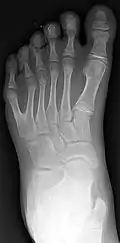

Classification is performed by using x-ray imaging to see the bone structures.[19]